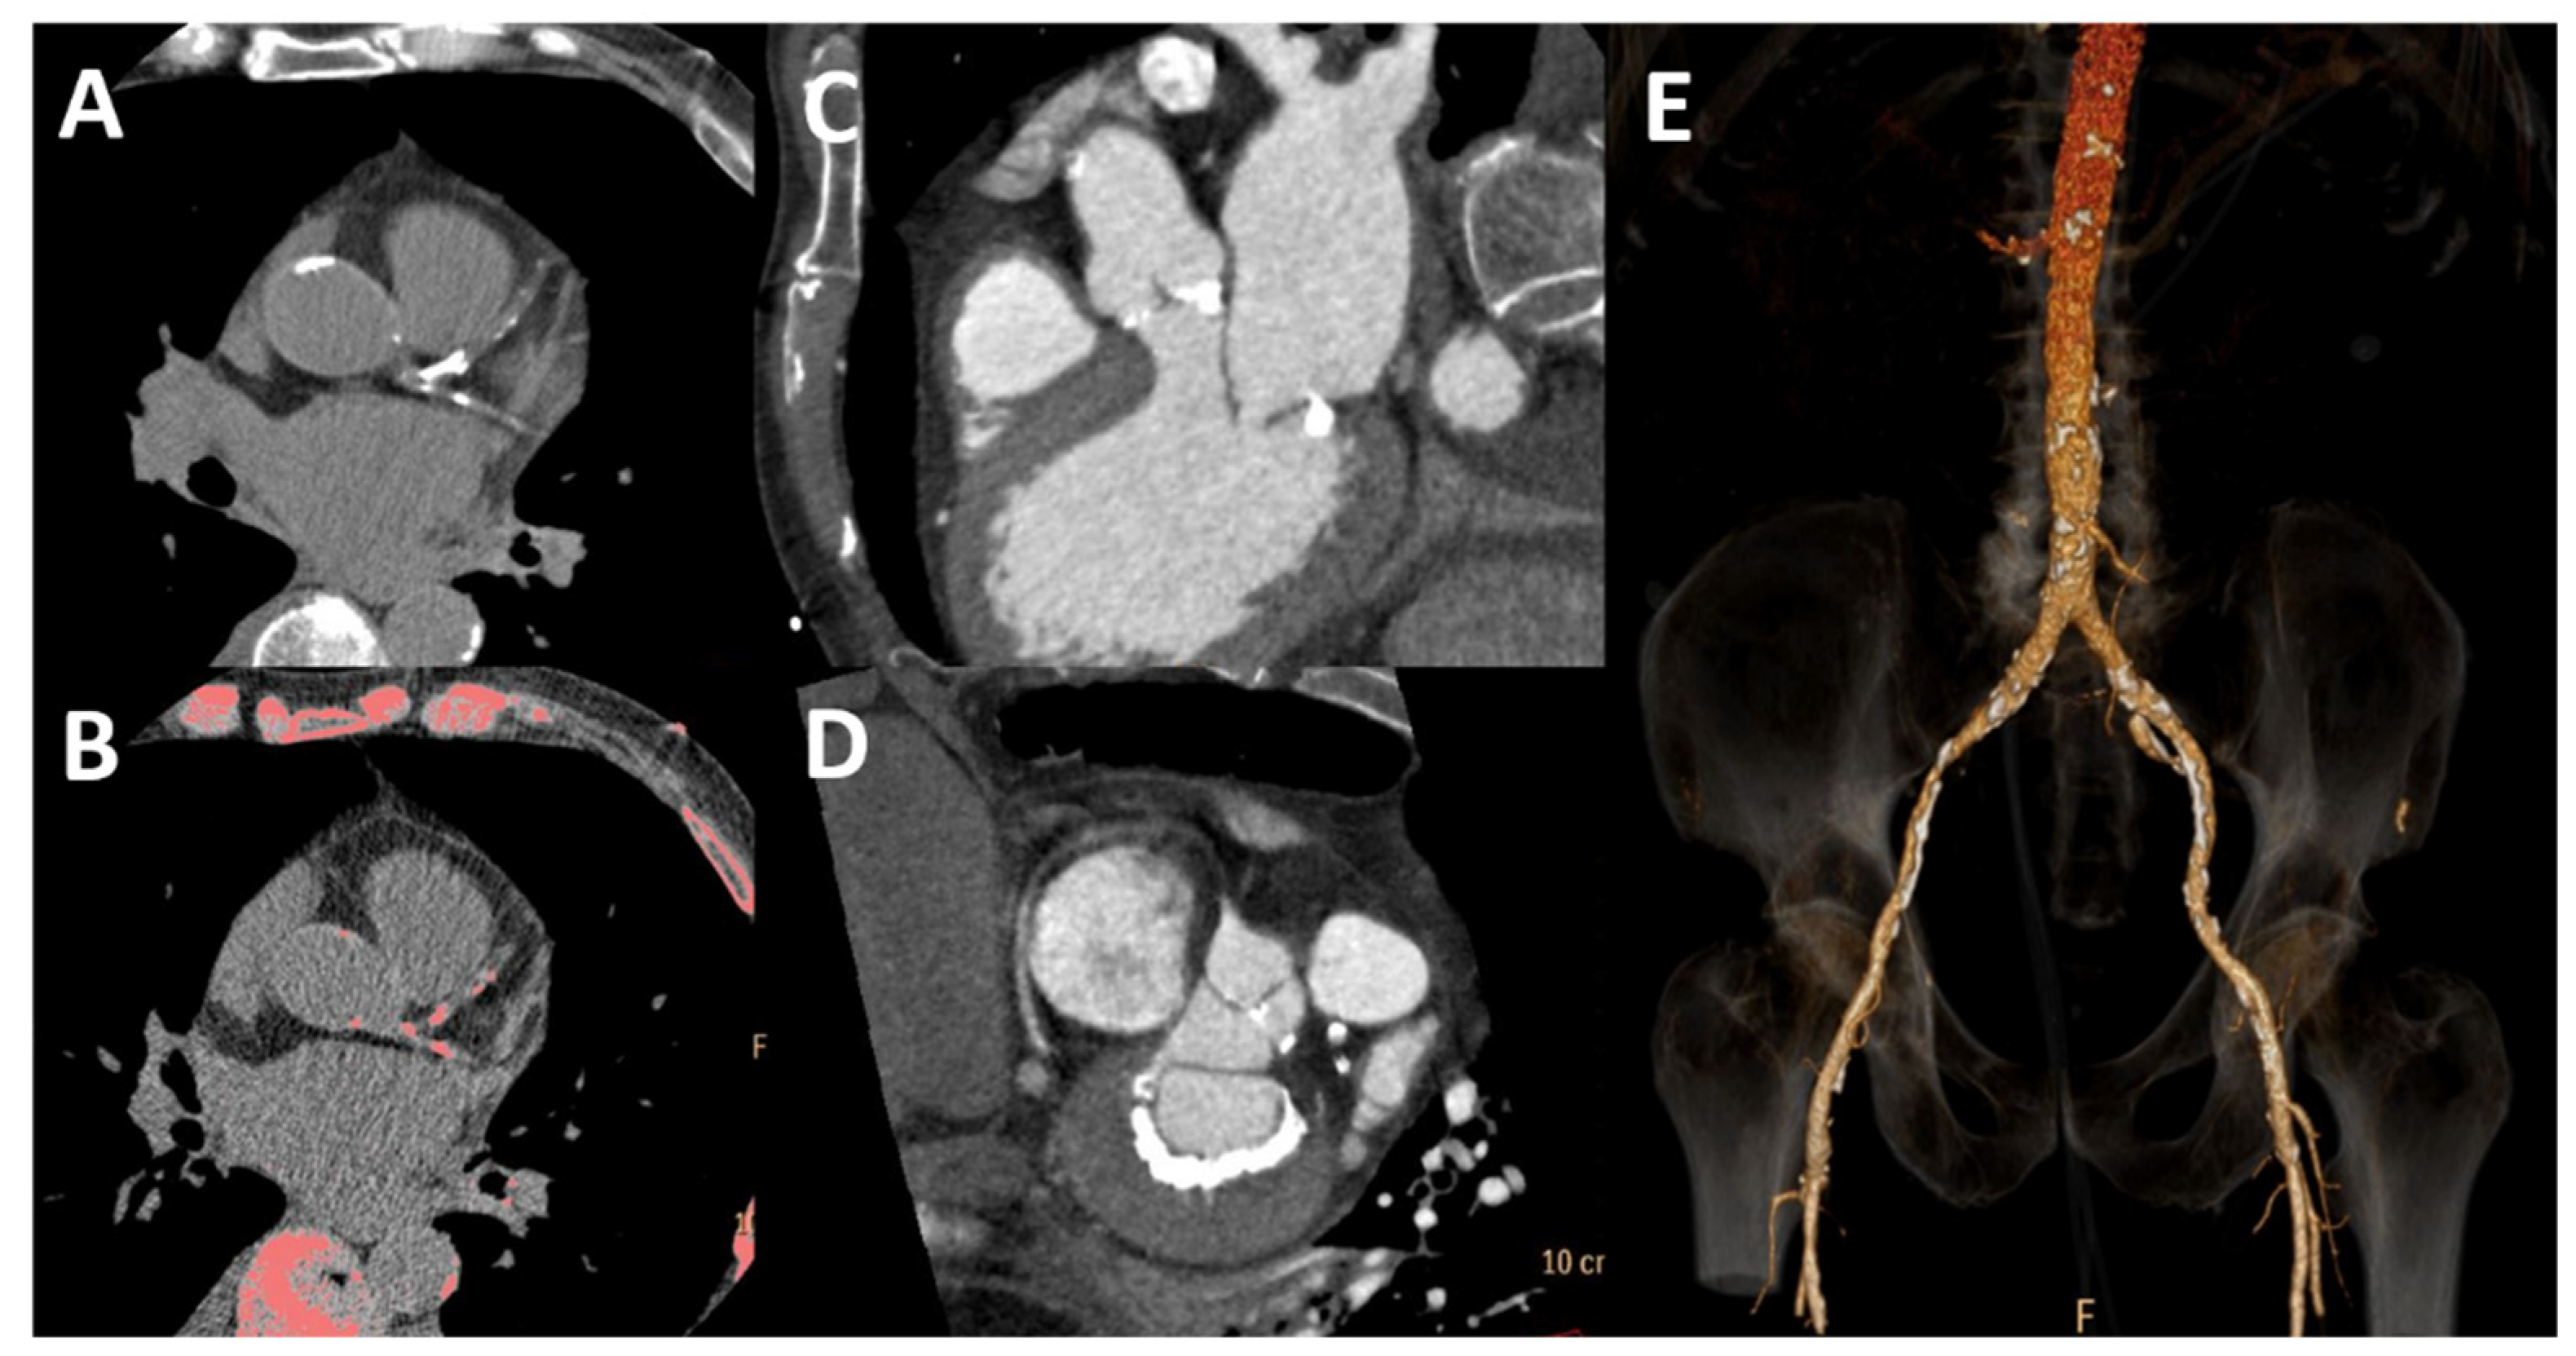

4. Computed Tomography

- Braun, J.; Oldendorf, M.; Moshage, W.; Heidler, R.; Zeitler, E.; Luft, F.C. Electron beam computed tomography in the evaluation of cardiac calcifications in chronic dialysis patients. Am. J. Kidney Dis. 1996, 27, 394–401. [Google Scholar] [CrossRef] [PubMed]

- Goodman, W.G.; Goldin, J.; Kuizon, B.D.; Yoon, C.; Gales, B.; Sider, D.; Wang, Y.; Chung, J.; Emerick, A.; Greaser, L.; et al. Coronary-Artery Calcification in Young Adults with End-Stage Renal Disease Who Are Undergoing Dialysis. N. Engl. J. Med. 2000, 342, 1478–1483. [Google Scholar] [CrossRef]

- Kramer, H.; Toto, R.; Peshock, R.; Cooper, R.; Victor, R. Association between Chronic Kidney Disease and Coronary Artery Calcification. J. Am. Soc. Nephrol. 2005, 16, 507–513. [Google Scholar] [CrossRef]

- Mukai, H.; Dai, L.; Chen, Z.; Lindholm, B.; Ripsweden, J.; Brismar, T.B.; Heimbürger, O.; Barany, P.; Qureshi, A.R.; Söderberg, M.; et al. Inverse J-shaped relation between coronary arterial calcium density and mortality in advanced chronic kidney disease. Nephrol. Dial. Transplant. 2020, 35, 1202–1211. [Google Scholar] [CrossRef]

- Russo, D.; Corrao, S.; Battaglia, Y.; Andreucci, M.; Caiazza, A.; Carlomagno, A.; Lamberti, M.; Pezone, N.; Pota, A.; Russo, L.; et al. Progression of coronary artery calcification and cardiac events in patients with chronic renal disease not receiving dialysis. Kidney Int. 2011, 80, 112–118. [Google Scholar] [CrossRef] [PubMed]

- Fujiu, A.; Ogawa, T.; Matsuda, N.; Ando, Y.; Nitta, K. Aortic Arch Calcification and Arterial Stiffness Are Independent Factors for Diastolic Left Ventricular Dysfunction in Chronic Hemodialysis Patients. Circ. J. 2008, 72, 1768–1772. [Google Scholar] [CrossRef] [PubMed]

- Furusawa, K.; Takeshita, K.; Suzuki, S.; Tatami, Y.; Morimoto, R.; Okumura, T.; Yasuda, Y.; Murohara, T. Assessment of abdominal aortic calcification by computed tomography for prediction of latent left ventricular stiffness and future cardiovascular risk in pre-dialysis patients with chronic kidney disease: A single center cross-sectional study. Int. J. Med. Sci. 2019, 16, 939–948. [Google Scholar] [CrossRef]

| Calcification | +++ | 2D-imaging | Yes | + | T1 and T2 weighted imaging | No | ++++ | Calcium score | Yes | [50,51,52,53,54,55,56,57,58,59,60,61,62,63] |

| Vascular stiffness | + | Tissue Doppler; speckle tracking | No | +++ | Phase-contrast imaging | No | ++ | Vascular calcification (indirect estimate) | Yes | [15,23,45,64,65] |